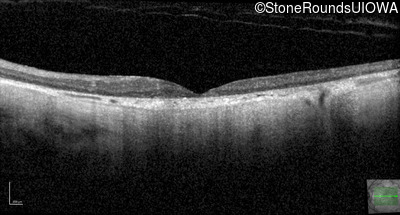

Optical Coherence Tomography - Right - 20/250 sc

Exemplar / OCT Stack